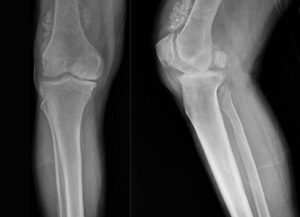

Diz ağrısı şikâyeti ile geldiği Düzce Üniversitesi Tıp Fakültesi Hastanesi’nde ameliyata alınan hastanın dizlerinden toplam 41 adet multipl sinovial kondromatozisi çıkartıldı. Özellikle diz eklemi çevresinde görülmekle birlikte kalça, dirsek ve diğer eklemlerde de görülen, ufak parçalardan oluşan cisimler olarak tanımlanan eklem faresi, eklem çevresinde eklem sıvısı ya da sinoviyumda görülen kıkırdak ya da kemik parçalarıdır. Eklem farelerinin boyutları birkaç milimetreden birkaç santimetreye kadar çıkabiliyor.